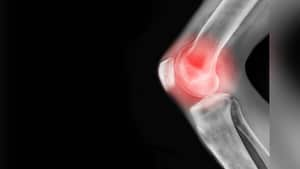

La artrosis de rodilla es una enfermedad articular que consiste en el deterioro del cartílago de forma progresiva. Esta patología degenerativa suele ser asociada a la vejez; sin embargo, hoy en día es frecuente encontrar pacientes jóvenes que presentan esta enfermedad.

Cuando se habla de artrosis de rodilla, el síntoma más habitual es el dolor articular, así como una limitación en los movimientos de las piernas, además este dolor está acompañado de crujidos y en ocasiones del llamado derrame articular, presentando rigidez, sensibilidad e hinchazón.

“En una articulación sana, los extremos de los huesos están cubiertos con un tejido suave y resbaloso llamado cartílago. El cartílago protege los huesos y les ayuda a deslizarse fácilmente cuando mueve la articulación. Con la osteoartritis, el cartílago se rompe y se vuelve áspero. En ocasiones, todo el cartílago se desgasta y los huesos se frotan entre sí, y pueden crecer protuberancias de hueso adicional en el área de la articulación llamadas espolones óseos”, explica la Biblioteca.

Así las cosas, explicó que la osteoartritis afecta a las personas de diferentes maneras y no todas tienen dolor, pero los síntomas más comunes son: Rigidez, especialmente durante los primeros 30 minutos después de levantarse del descanso.

- Inflamación de las articulaciones, especialmente después de usar mucho la articulación.

- Menos movimiento de lo normal en la articulación.

- Una articulación que se siente floja o inestable.